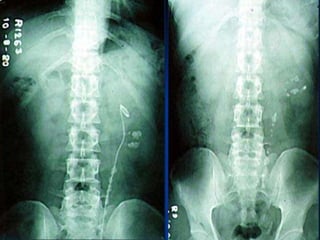

Percutaneous nephrolithomy PCNL  The key-hole surgery

Indication of PCNL:  >2.5-3.0 cm failure of ESWL (matrix,cystine,ca oxalate monohydrate) cystine stone >1.5 cm lower calyx stone ≥ 2.0cm(narrow, long, acute angel infuldibulopelvic angel) caliceal diverticulum UU stone >1cm not respond to ESWL or difficult with URS.